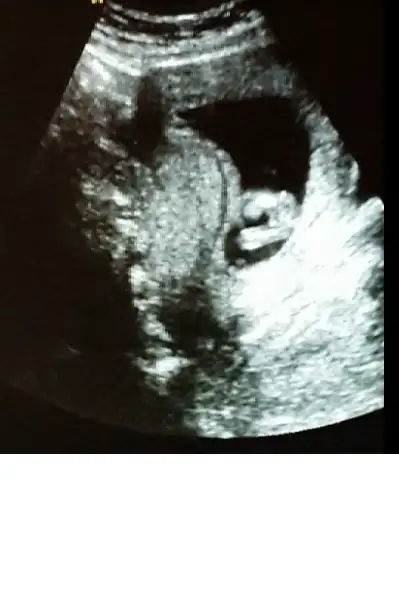

Gijnij merhaba ben seni ve buranin sıkı takipcilerindenim benim de 2 kizim var ALLAH nasip ederse 3 cuye hamileyim 14 haftalik rica etsem resimi eklesem bana yorum edermisin image.webp

ben mesaj atmıştım sana ama sorun oldu gitmedi sanırım. bu fotoda ben nubu çözemedim canım

Sagolasin canim yorumun icin ben 13 haftalikken gittigimde ozeldeki doktor yuzde yetmis erkek demisti 2 li icinde devlete gittim soylemedi ondan merak ettim sordum cnm bu arada senin bana msjin gelmedi gelseydi soylerdim cnm

Bebeğin kız canım hayırlı olsun inşallah

bak buda bacak arası. ama video çekmiştik sanki pipi var gibi geldi bana. acaba kordon mu o? çok kalındı zaten keşke videoyu gönderebilsem sana :).. bu arada yorumun için çok teşekkür ederim canım:KK68:

Eklentiler

• tp.webp

tp.webp

12,6 KB · Görüntüleme: 194

Canım kızda da erkekte de bu haftalarda çıkıntı oluyor sadece kızın çıkıntılı karşıya bakıyor erkeğin yukarı doğru senin o pipi gibi gösterdiğin karşıya bakıyor kız gibi yani yinede yanılma payı vardır mutlaka